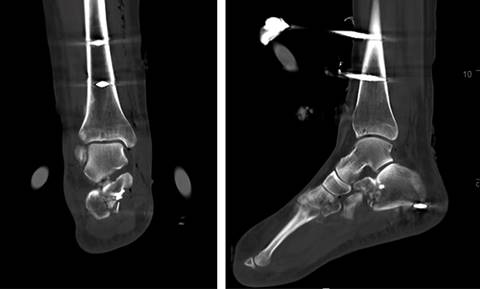

Las radiografías de tobillo y pie mostraron una subluxación tibioastragalina junto a una luxación subastragalina lateral (Figura 2). Se decidió completar el estudio con una TAC (Figura 3), que demostró una fractura del sustentaculum tali y un arrancamiento en el canto posterior del maléolo peroneo (fleck sign) sugestiva de afectación del canal retromaleolar (Figura 4).

Figura 3: Corte coronal (A) y axial (B) de la tomografía axial computarizada. Luxación lateral subastragalina junto a fractura del sustentaculum tali.